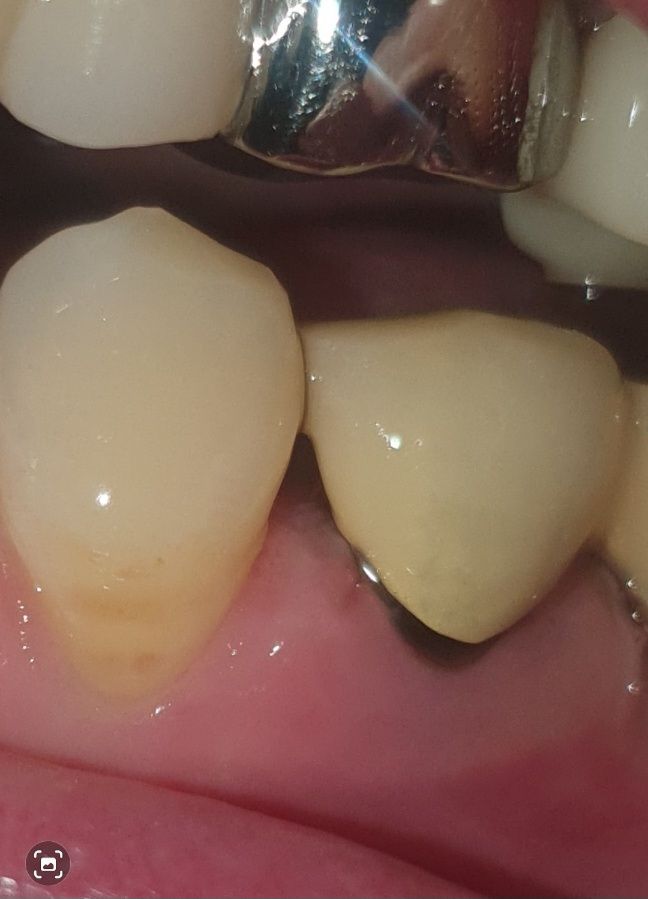

치주염 치과의사 선생님 계실까요~?

다름이 아니오라 예전에 신경치료후 크라운으로 덮어 씌웠습니다.

하지만 앞자연치아의 공간 사이와 크라운치아가 조금 벌어져있게 제작되었습니다.

그래서 저 사이의 공간이 좀 있는편이라 거기에 음식물 찌꺼기가 많이 끼는 편입니다.

이에 치실을 하루 한번 하는편인데, 잇몸이 조금 내려가는 기분이 들어서 이렇게 사진을 올리게 되었습니다.

혹시 치주염인지 봐주실 치과의사 선생님 계실까요..? ㅠㅠ..

• 2번 째 사진

해당 부위에서 출혈이나 농이 나온다면 치주염을 의심해볼 수 있습니다. 잇몸에 붓기 등은 있어보입니다.

보철물을 만들떄 무조건 치아 사이를 완전히 메꾸는건 아닙니다. 아마 처음에는 저정도 공간은 아니엿지만 시간이 지나면서 잇몸이 내려가면서 공간이 더 넓어진거 같습니다.

현재로써는 잇몸이 많이 내려와 있어보이지는 않으나, 이 공간이 음식물 찌꺼기로 인해 염증을 유발될수 있습니다.